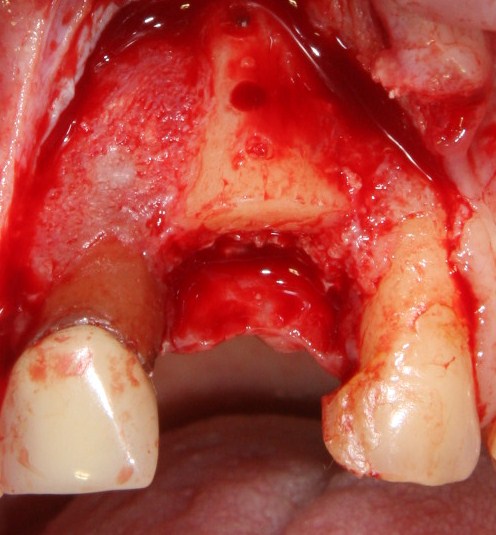

Делаем разрез в пределах кератинизированной десны. Скелетируем кость, видим следующее:

По краям от лунки видны остатки прошлых операций. Это не кость, а грануляции вперемежку с твердыми частичками биоматерила. Жди мы хоть несколько лет — вряд ли они организовались в приемлемую для имплантации костную ткань. Поэтому мы всё вычищаем, до естественной кости:

Ее объем, как мы видим, небольшой, использовать его для ПРАВИЛЬНОЙ установки импланта нереально. Почему выделил слово «ПРАВИЛЬНОЙ»? Потому что некоторые типы имплантационных систем позволяют установить имплантат хоть куда, хоть в какой объем кости, если очень хочется, конечно. Но ведь у нас нет задачи «воткнуть» имплантат всеми правдами и неправдами, верно? Комплексная цель лечения — воссоздание полноценно функционального зуба со всеми окружающими тканями. Чем мы, собственно, и занимаемся.